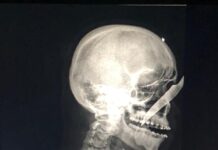

Homem fica com uma faca encravada no nariz no Amazonas

Alberto Carvalho de Oliveira, de 25 anos, recebeu uma facada no rosto que ficou cravada no nariz de um homem identificado como sendo André...